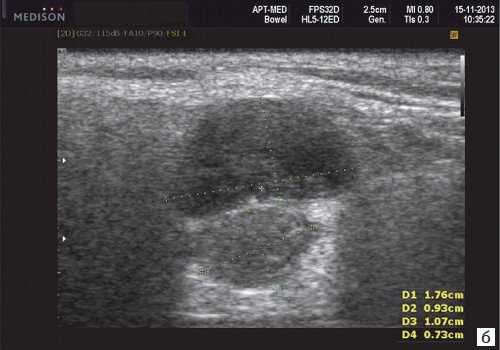

Морфология. Малая плеоморфная аденома: одиночная, цельная, яйцевидная и хорошо разграниченная опухоль. Большая плеоморфная аденома на УЗИ: дольки ± кровоизлияние или некроз ± кальцификация

Серошкальное УЗИ. Хорошо выраженная, солидная и гипоэхогенная по сравнению с прилегающей тканью слюны. Однородная внутренняя эхо-структура с задним акустическим усилением. Опухоль имеет несколько тканевых границ и позволяет звуку легко проникать, вызывая улучшение заднего отдела. Большие опухоли могут иметь неоднородные внутренние эхосигналы из-за кровоизлияния и некроза. Гетерогенная плеоморфная аденома может иметь нечеткие границы, имитирующие злокачественную опухоль. Большие опухоли могут иметь дольки и появляться на ножке. Необычный кальциноз при ультразвуковом сканировании наблюдается при давней опухоли. Кожа и подкожные ткани в норме

Плеоморфная (полиморфная) аденома (смешанная опухоль СЖ) - аденома СЖ, построенная из двух типов клеток: эпителия протоков и миоэпителиоцитов. Макроморфологическая картина. Опухоль обычно представляет собой эластичный или плотный узел дольчатой серовато-белой ткани, как правило, инкапсулированный частично. Типичной для плеоморфной аденомы является так называемая хондроидная строма, напоминающая гиалиновый хрящ. Варианты эхографического изображения плеоморфных аденом представлены на рисунке 8.